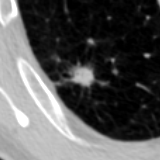

The current study focuses on lung nodule retrieval from a database of CT scans, where patches taken from CT slices of pulmonary nodules are to be mapped into an embedding. LIDC-IDRI [5] is a dataset of thoracic CT scans of 1,010 patients. All the scans were annotated by up to four radiologists, where each one identified, segmented and evaluated separately the lung nodules of a diameter above . Their evaluation also included ratings for a set of 9 characteristics: Subtlety, Internal structure, Calcification, Sphericity, Margin, Lobulation, Spiculation, Texture and Malignancy. The rating system was based on a discrete score of 1-5. Four examples of nodule patches are illustrated in Figure 2: 2 benign (a, b) and 2 malignant (c, d). A rounded vector of the mean rating is bellow each nodule, with the characteristics ordered according to the listing above. The most prominent difference between a and b is the calcification: 3 (solid) and 6 (absent) accordingly. d compared to c has a more defined margin, is more lobulated, but less spiculated. The malignancy score is used to define malignancy classes: score of 1-2 is benign, score of 3 is unknown, and a score of 4-5 is malignant.

(a) Benign

3, 1, 3, 3, 4, 3, 1, 5, 1

(b) Benign

3, 1, 6, 5, 5, 1, 1, 5, 2

(c) Malignant

5, 1, 6, 3, 3, 4, 1, 5, 5

(d) Malignant

4, 1, 6, 3, 4, 2, 2, 5, 4